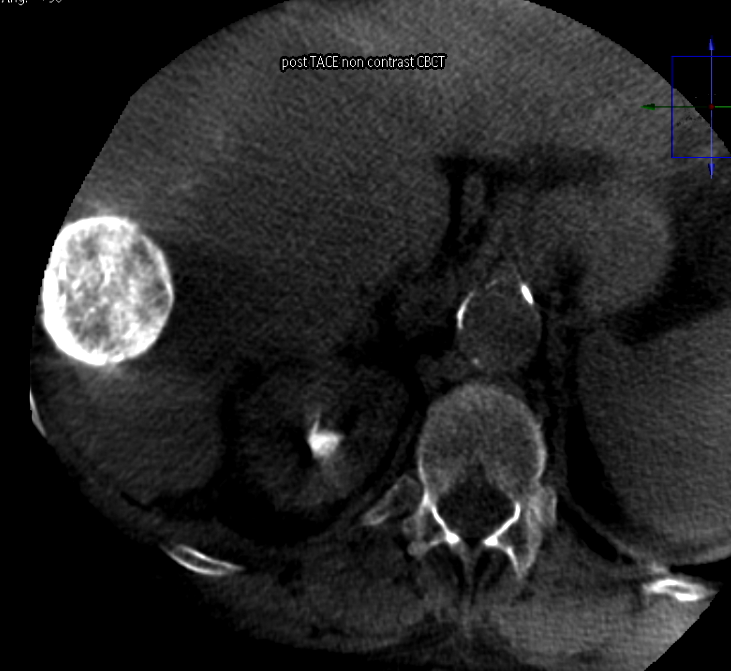

My perfect sphere HCC TACE

#radreshttps://twitter.com/bonesz/status/1207425485078224897 …